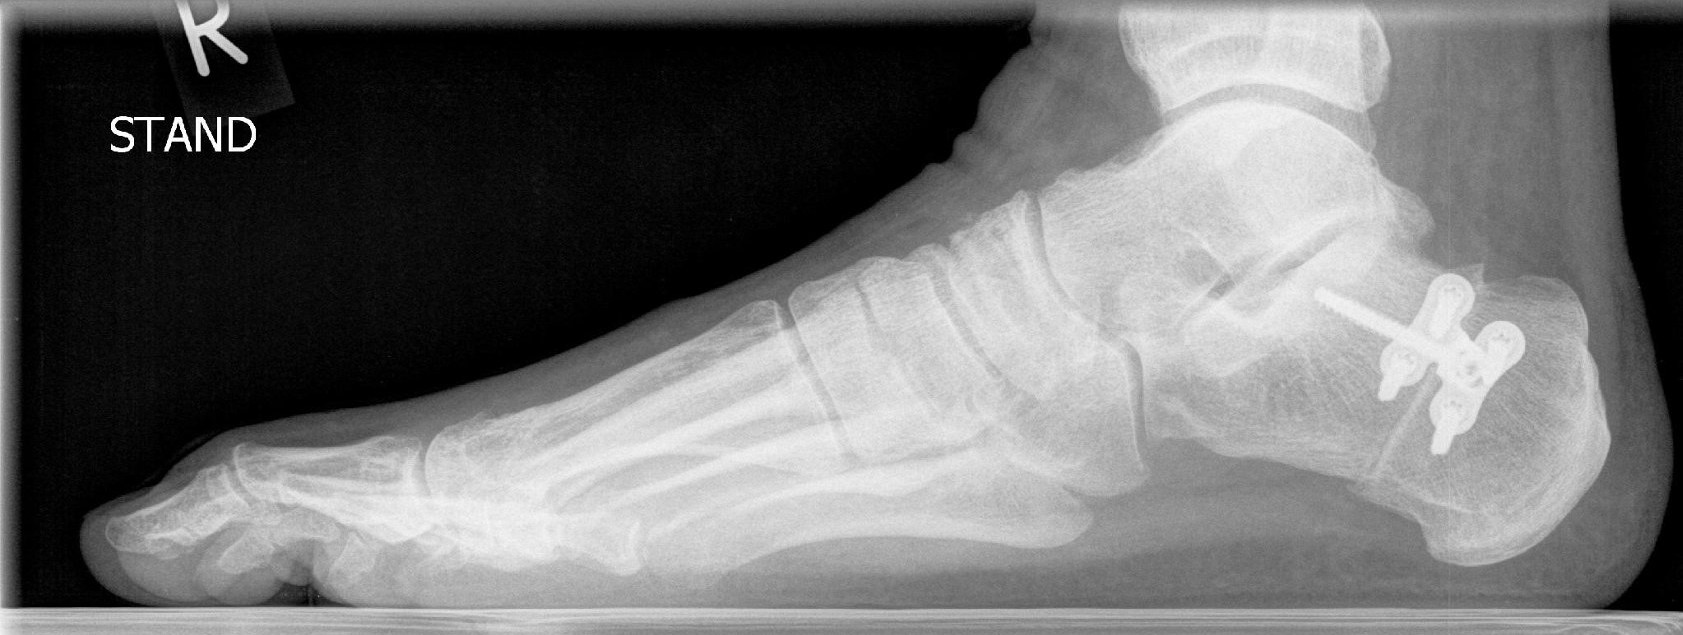

Um festzustellen, ob eine Hallux valgus-Deformität vorliegt, erfolgen zunächst ein Anamnesegespräch sowie eine ausführliche Untersuchung beider Füße in stehender Position. Häufig ist die Erkrankung dabei schon deutlich zu erkennen. Zur Planung der Therapie kommen darüber hinaus Röntgenaufnahmen des betroffenen Fußes zum Einsatz. Eine Schnittbilddiagnostik (CT, MRT) ist in der Regel nicht erforderlich.

Für die Behandlung eines Hallux valgus stehen je nach Ausmaß der Erkrankung verschiedene Operationstechniken zur Verfügung: Im einfachsten Fall lassen sich das Köpfchen des ersten Mittelfußknochens verschieben (Osteotomie) und Weichteilschäden operativ korrigieren.

In ausgeprägten Fällen kann eine Korrektur im Mittelfuß-Schaftbereich oder sogar eine Versteifung des Verbindungsgelenks zwischen Fußwurzel und Mittelfuß erforderlich werden. Das Ergebnis der Korrektur wird durch spezielle Metallimplantate gesichert. Diese sind dank moderner Entwicklungsmethoden sehr dünn, sodass keine Weichteilirritationen entstehen. Gleichzeitig wird die erforderliche Stabilität gewährleistet.

Behandlung eines einfachen Falls des Hallux valgus | Behandlung eines ausgeprägten Falls des Hallux valgus |